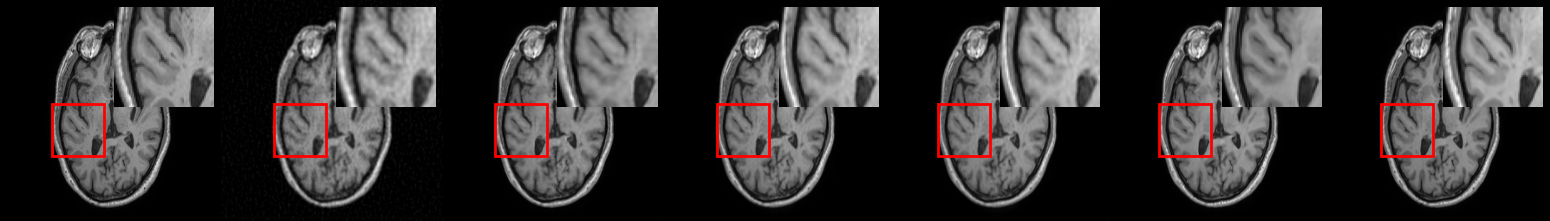

4.2 MRI Reconstruction

Quantitative results for MRI reconstruction are summarized in Table 1. On average, BCDM achieves (pSNR, SSIM, FID) improvements of (4.9dB, 2.1%, 40) over post-conditioned DMs (i.e., DPS, DMPS) and (5.7dB, 1.7%, 23.5) over the conditional DM baseline (i.e., DI). Representative reconstructions in Fig. 2 highlight that BCDM yields superior image quality against competing methods with minimal artifacts and acute structural details. While DI is a conditional DM, it cannot alleviate the global aliasing artifacts in accelerated MRI.

Quantitative results for image deblurring are summarized in Table 1. On average, BCDM achieves (pSNR, SSIM, FID) improvements of (2.5dB, 5.1%, 19.6) over post-conditioned DMs, and (0.3dB, -0.4%, 3.8) over DI (albeit DI yields slightly higher SSIM). Note that image blur is a local artifact that DI can more effectively cope with. However, unlike BCDM, DI still fails to provide theoretical guarantees for learning the true conditional score-function. Fig. 2 displays representative images from competing methods. While averaging across independent samples tends to improve image quality for all methods, BCDM shows notably lower artifacts than competing methods in single image instances.

Quantitative results for image super-resolution (SR) are summarized in Table 1. In this task, the unrolled method performs more comparably with diffusion methods in terms of pSNR and SSIM, and DI yields the highest performance while BCDM performs competitively with generally second-best metrics among DMs. It is important to note that the common quantitative metrics reported here provide global performance measures that are insufficiently sensitive to detailed image features, thus visual evaluations serve a critical role in comparative assessments, especially for the SR task where high-frequency features are recovered in the absence of high-frequency data. In terms of visual quality, we find that BCDM outperforms competing methods in spatial acuity, particularly near heterogeneous regions containing object boundaries, as exemplified in Fig. 2.

Finally, to assess the effects of domain shifts in the forward operator on reconstruction performance, we conducted an image inpainting experiment. The domain shift was obtained by using larger pixel-removal masks during training than those prescribed during testing. Note that knowledge of the forward operator only influences conditional DMs, while unconditional DMs are not affected (i.e., DPS, DMPS). Quantitative metrics are summarized in Table 2. The unrolled method is a deterministic approach so it faces difficulty in filling in the masked image region. On average, BCDM achieves (pSNR, SSIM, FID) improvements of (2.9dB, 6.2%, 15.9) over post-conditioned DMs, and (9.7dB, 4.9%, 269.4) over DI. These results suggest that BCDM is more resilient against domain shifts in the forward operator than other DMs. In terms of visual quality, BCDM substantially outperforms competing methods in terms of accuracy of structural details, as seen in Fig. 2.